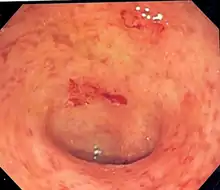

| Endoscopic image of a colon affected by ulcerative colitis. The internal surface of the colon is blotchy and broken in places. Mild-moderate disease. | |

Endoscopic

The best test for diagnosis of ulcerative colitis remains endoscopy, which is examination of the internal surface of the bowel using a flexible camera. Initially, a flexible sigmoidoscopy may be completed to establish the diagnosis.[73] The physician may elect to limit the extent of the initial exam if severe colitis is encountered to minimize the risk of perforation of the colon. However, a complete colonoscopy with entry into the terminal ileum should be performed to rule out Crohn's disease, and assess extent and severity of disease.[73] Endoscopic findings in ulcerative colitis include: erythema (redness of the mucosa), friability of the mucosa, superficial ulceration, and loss of the vascular appearance of the colon. When present, ulcerations may be confluent. Pseudopolyps may be observed.[74]

Ulcerative colitis is usually continuous from the rectum, with the rectum almost universally being involved. Perianal disease is rare. The degree of involvement endoscopically ranges from proctitis (rectal inflammation) to left sided colitis (extending to descending colon), to extensive colitis (extending proximal to descending colon).[14]